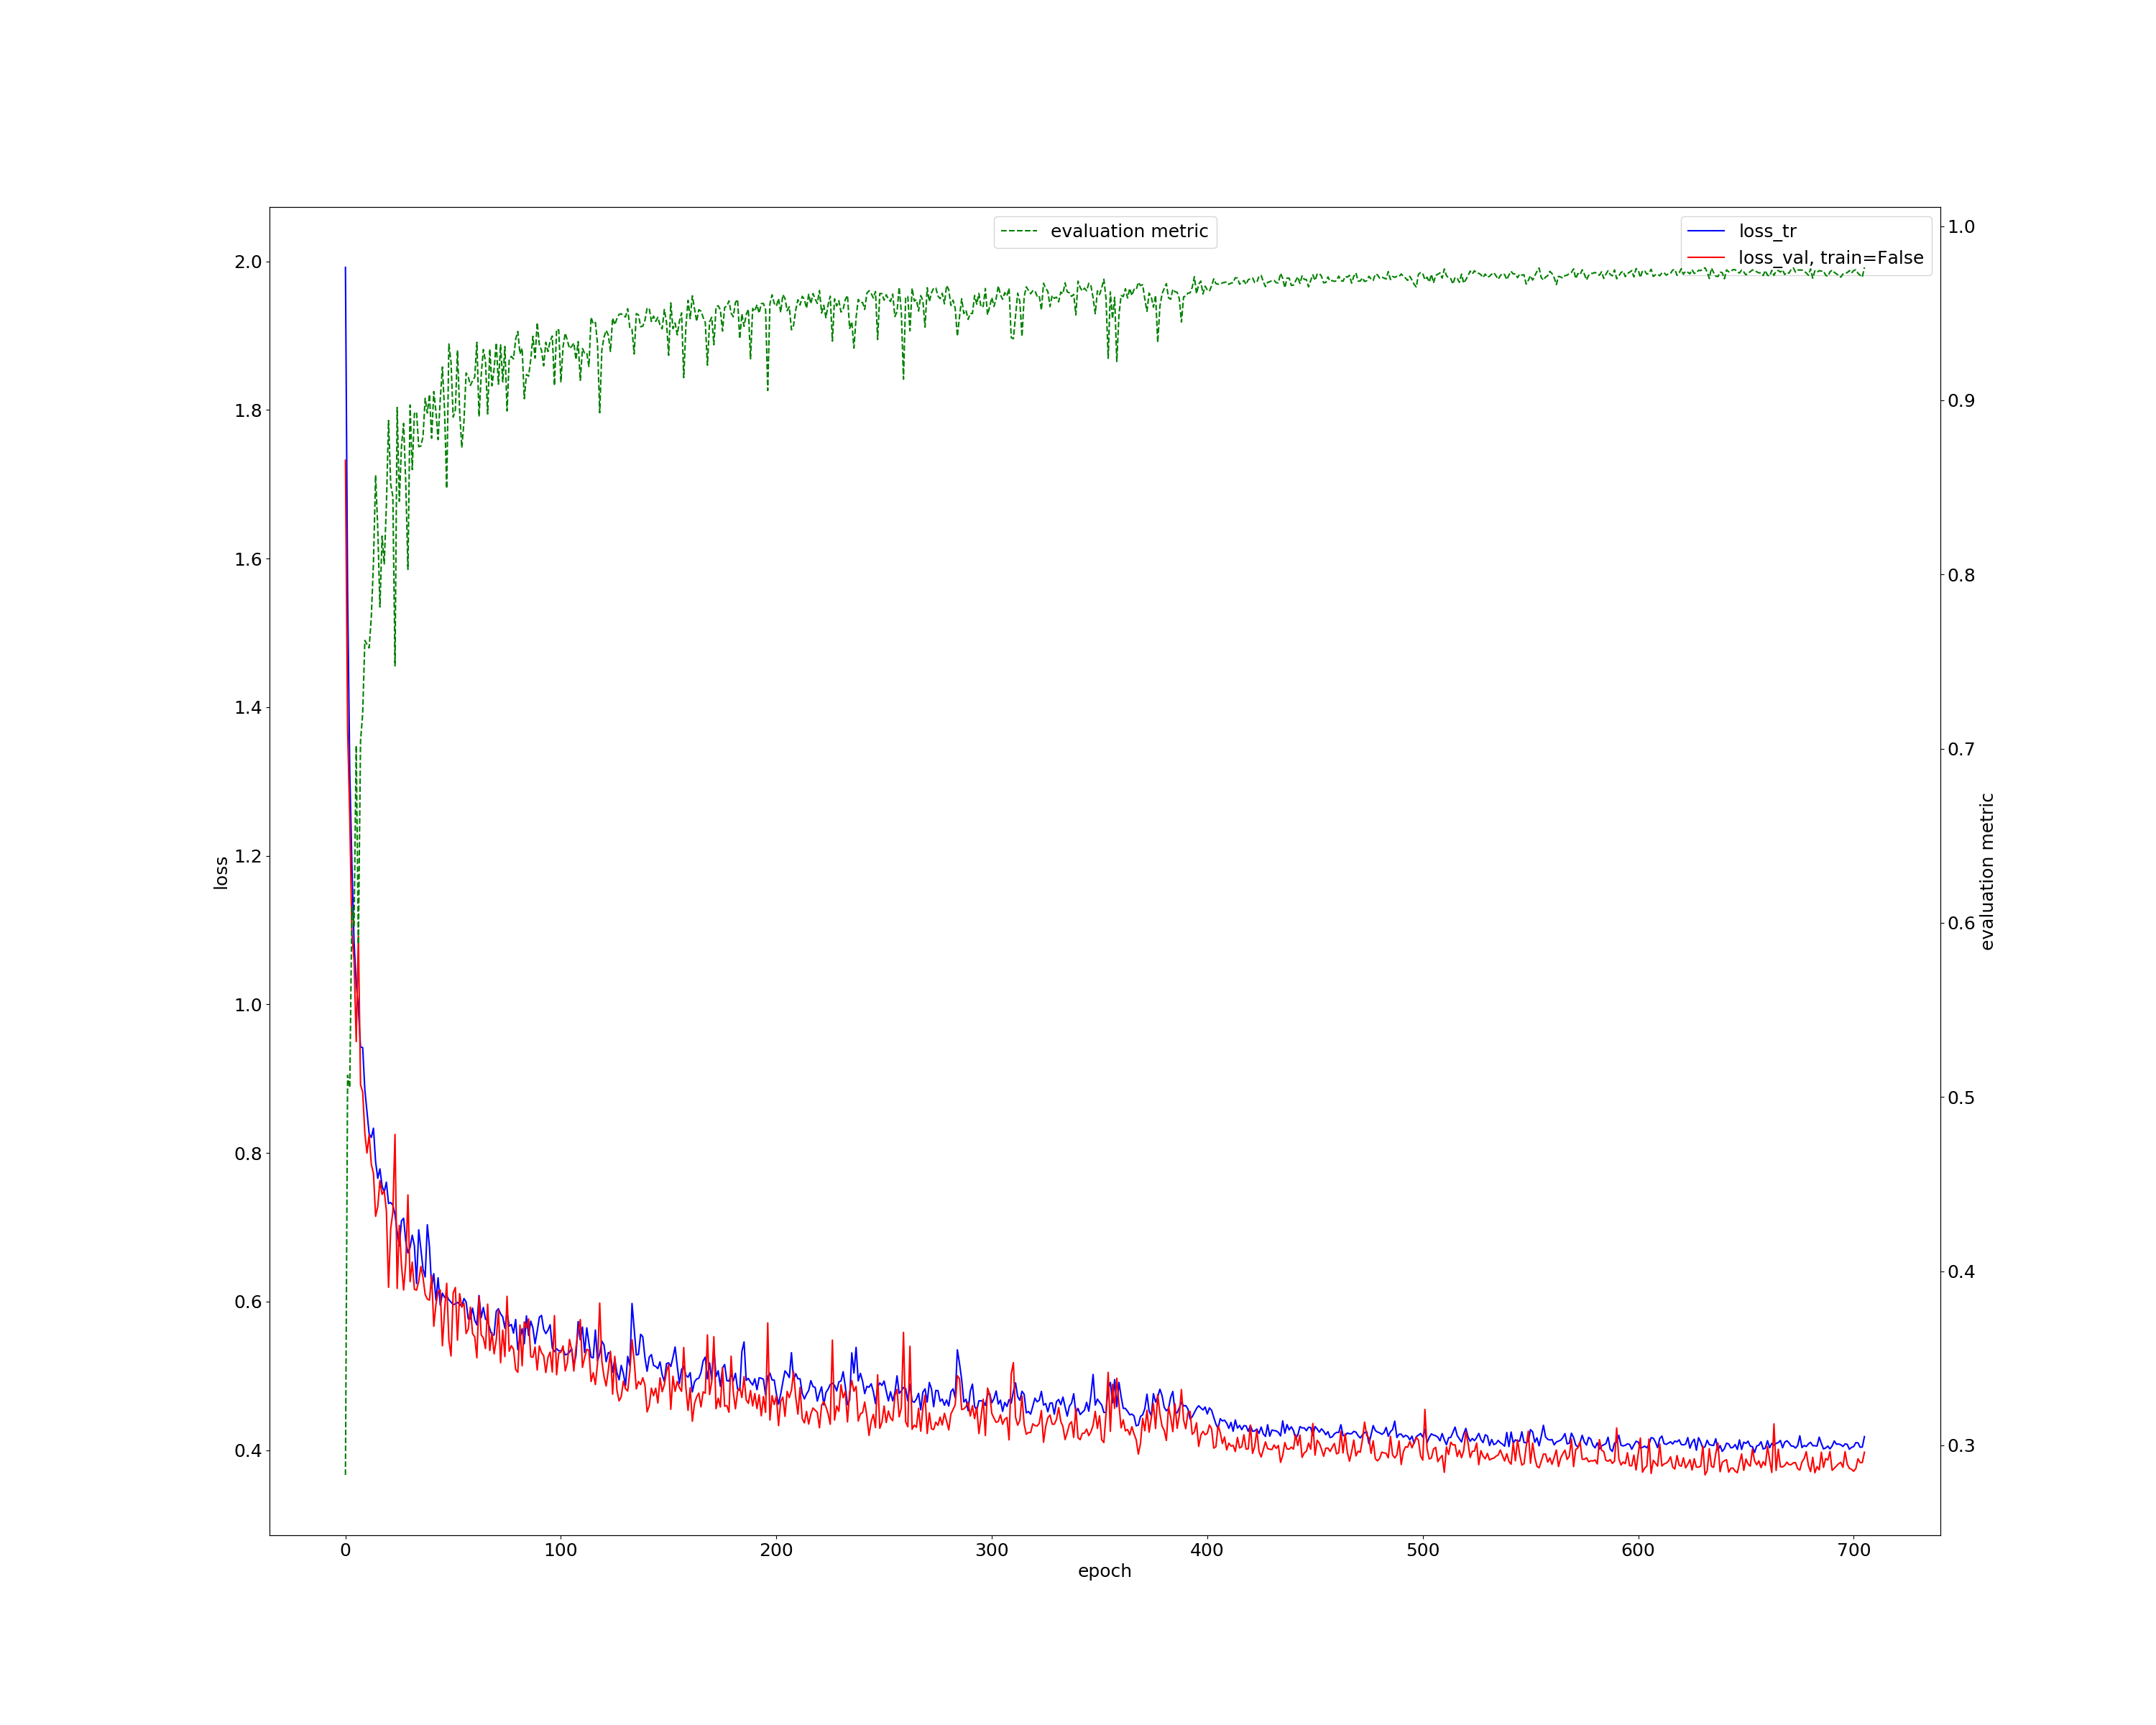

There are 210 patient CT scans published to train models. We divided 42 of these to be the test dataset and used other images to train our model. It consumed about 5 days running on 2 GPUs (Tesla 32GB). The loss during training is shown as Fig. 3. Stable reduction of our proposed loss could be obversed, and this process continued for about 700 epoches when the learning rate got the end of our patience.